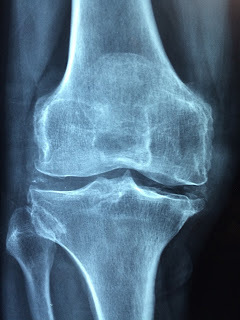

Артроз и артрит - это заболевания суставов. Вернее это то, что уничтожает клетки хрящевой ткани и не даёт им полноценно восстановится. Вот только артроз - это всё-таки возрастное заболевание, а артрит может возникнуть в любом возрасте. В медицине есть такое понятие, как "ювенальный артрит".

Поскольку дегенеративные изменения в суставах значительно снижают качество жизни и ограничивают работоспособность, приводя к инвалидности, особенно в экономически развитых странах, то, естественно, это отражается на экономике целой страны. Так, в США очень серьезно относятся к этой проблеме, артрит и артроз оказывают, примерно, такое же действие на экономику, как умеренный экономический спад. Пенсии по инвалидности, очень дорогое лечение и страховые выплаты очень сильно бьют по бюджету Соединённых Штатов.